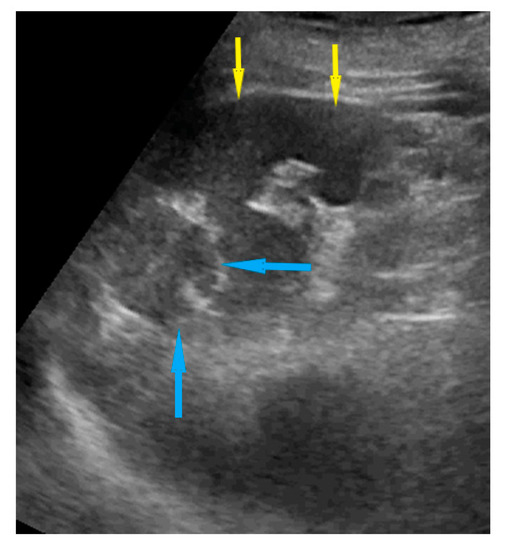

| Omentum | Focal infiltration of omentum: hypoechogenic nodules with discrete vascularization. Diffuse infiltration: omental cake appears as a nodular, perfuse, and non-peristaltic tumor that is located between the anterior abdominal wall and bowel loops. | Figure 1 | Video S1 |

| Small bowel mesentery root | Involvement is suspected when bowel loops have poor mobility and are “fixed together” in the dynamic ultrasound examination with a cauliflower-like image. | Figure 2 | Video S2 |